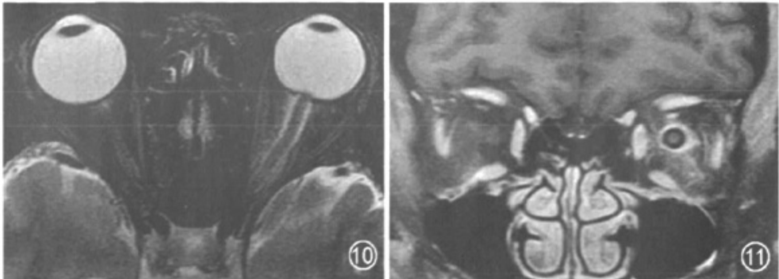

视神经脊髓炎(Neuromyelitisoptica,NMO)是一种中枢神经系统(CNS)自身免疫性疾病,其主要特征为同时或连续发生的急性视神经炎(ON)和横贯性脊髓炎(TM)。本文总结了视神经脊髓炎发病的机制、临床表现、鉴别诊断、评估方法和康复治疗方法。